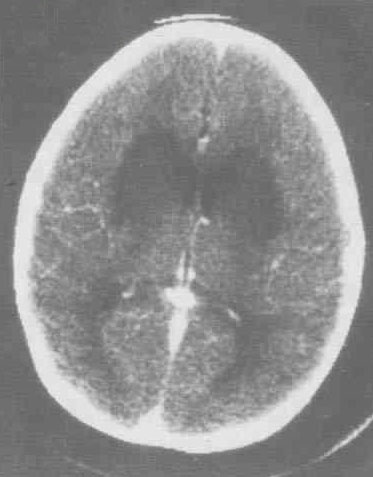

腦炎指的是腦實(shí)質(zhì)炎癥性病變,大多數(shù)的腦炎都是由病毒引起的,部分可能與霉菌、細(xì)菌、寄生蟲(chóng)感染、變態(tài)反應(yīng)性的疾病有關(guān)。腦炎都指的是病毒性的腦炎,病毒性腦炎也可以分為幾種: